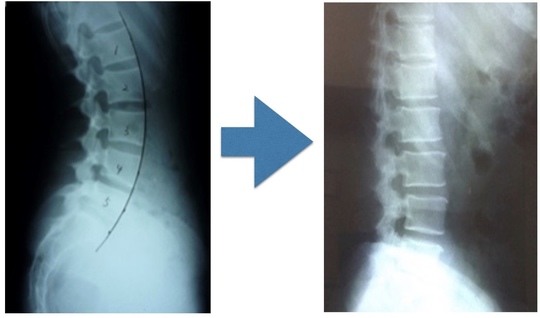

脊柱がまっすぐストレートになっている腰痛

フラットバックと腰痛の関係性

フラットバックといい、脊柱がストレート方向になることをいいます。

脊柱がまっすぐだと、どのようなデメリットがあるのか!

脊柱は、頸椎軽度前弯 胸椎軽度後弯 腰椎軽度前弯となっております。

軽い弯曲を形成しています。

それには理由があり、衝撃や外力から脊柱がたわんで力を分散させる役割があります。

その分散させる役割があるのに脊柱がまっすぐだと、外力に対して分散させることができないため局所へのストレスが高まります。

局所へのストレスが高まるとヘルニアだったり、圧迫骨折、腰痛、首痛、股関節痛などを発症します。